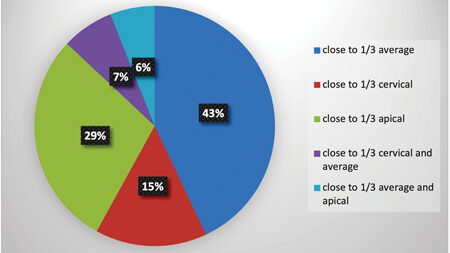

We are living in a new chapter of human development. Known as the Fourth Industrial Revolution, it represents a fundamental change in how we live, work and relate to one another.1 This change is enabled by extraordinary technology, which blurs the physical, digital and biological worlds in ways that create both prodigious progress and potential … Read more